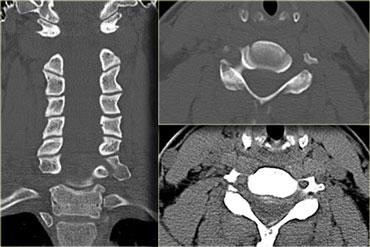

Trật khớp mặt hai bên (Bilateral Interfacetal Dislocation)

Trật khớp mặt hai bên (BID) là hậu quả của tăng gấp cực độ.

Có sự trật khớp ra trước của các khối khớp kèm phá vỡ phức hợp dây chằng phía sau, dây chằng dọc sau, đĩa đệm và thường cả dây chằng dọc trước.

Khi trật khớp hoàn toàn, đốt sống bị trật di lệch ra trước một nửa đường kính trước-sau của thân đốt sống.

Do tổn thương mô mềm lan rộng và trật khớp mặt, BID là chấn thương không vững và có tỷ lệ cao tổn thương tủy sống kèm theo.

Các dấu hiệu bao gồm:

- Trật khớp mặt hai bên.

Di lệch ra trước 50% tại C5-C6 do trật khớp.

Trong trật khớp một bên, mức độ di lệch ra trước thường chỉ là 25%. - Khoang gian gai giữa C5 và C6 rộng ra do đứt dây chằng.

- Rách khoang đĩa đệm.

Bên trái là hình CT của cùng bệnh nhân, xác nhận trật khớp hai bên.

Gần một trong các khớp mặt có một mảnh xương nhỏ, nhưng không có gãy xương lớn, vì vậy về cơ bản đây chỉ là chấn thương mô mềm tăng gấp.